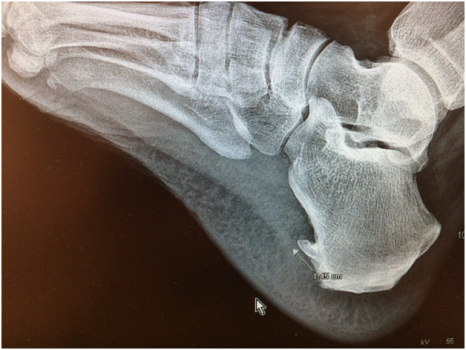

3) По данным рентгенографии диагностирована крупная пяточная шпора – более 1 см.

На основании клинико-анамнестической и инструментальной картины установлен клинический диагноз: Пяточная шпора слева, плантарный фасциит.